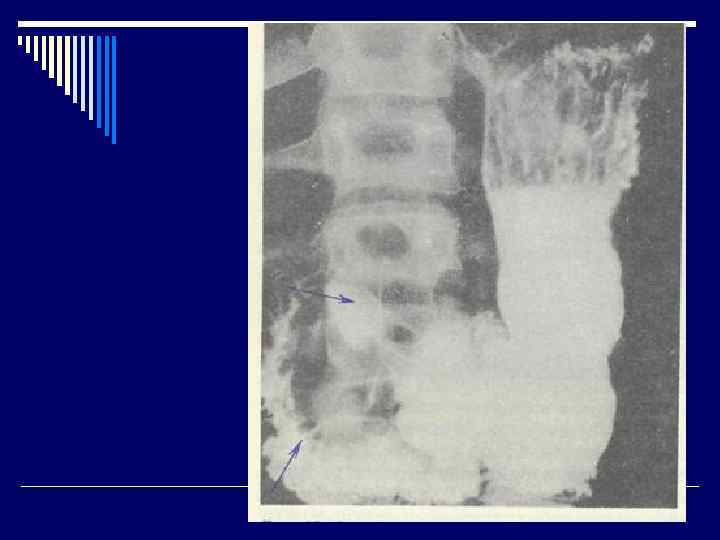

Инвазивные методы: быстрый уреазный тест, бактериоскопический, бактериологический, гистологический (“золотой стандарт”). Неинвазивные методы: - серологический; - дыхательный; - метод полимеразной цепной реакции - Интрагастральная р. Н-метрия - Рентгенологические исследования (по показаниям). - Ультразвуковое исследование органов брюшной полости.

Язва желудка (язвенная болезнь желудка) (Шифр R 25) Язва двенадцатиперстной кишки (язвенная болезнь двенадцатиперстной кишки) (Шифр R 26) o Язвенная болезнь (ulcus gasteris et duodeni) (пептическая язва)– хроническое рецидивирующее заболевание организма, которое характеризуется формированием язвенного дефекта слизистой оболочки желудка или двенадцатиперстной кишки, склонное к прогрессированию, сопроваждается болевым, диспепсическим, интоксикационным синдромами, нарушением секреторной и моторной функции желудка.